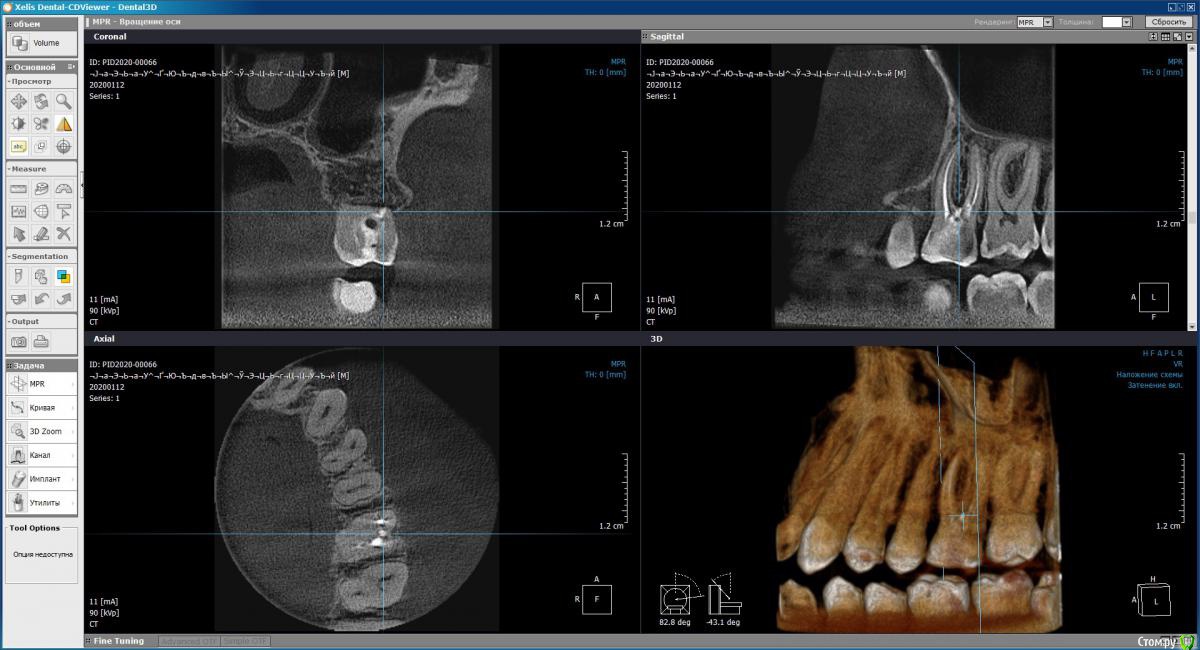

Demon_L Опубликовано 23 января, 2020 Поделиться Опубликовано 23 января, 2020 (изменено) Мне 36 лет, примерно 12 лет назад залечивал зуб (верхняя левая 6-ка), запломбировали 3 канала гуттаперчей, поставили обширную световую пломбу в хорошей платной клинике.Позже я стал замечать, что зуб немного темнее остальных, но не придавал этому значения, т.к. зуб не беспокоил. На днях откололся небольшой кусочек от этого зуба, пошел в клинику, сделали снимок КТ, сняли пломбу. Вердикт - 3 канала не требуют перелечивания, но есть 4-й канал, который требует лечения и который не нашли первый раз. Но что самое печальное - обнаружили перфорацию дна полости, которую по ошибке сделали при первом лечении, видимо когда искали 4-й канал. Тогда же видимо и положили раствор резорцин-формалина, что и придало темный с отттенками красного цвет зубу.Пока не нашли перфорацию, по снимкам склонялись к установке коронки, но после того, как обнаружили, один врач настойчиво рекомендовал удаление и имплантат, другой допускает коронку, но тоже рекомендует имплантат.Хотел бы спросить Вашего мнения, действительно ли при наличии перфорации дна полости (она небольшая, но файл в неё проходит и выступает капелька крови) ставить коронку противопоказано?Можно ли сначала залечить перфорацию, а потом ставить коронку? Прибегать к удалению и имплантации хотелось бы в последнюю очередь.Прилагаю несколько снимков КТ. Если они недостаточно информативны, готов выложить с любого другого ракурса. Могу вообще поделиться isо-файлом со снимком (образ CD), тогда можно будет покрутить в 3D как угодно у себя на ПК (запускается автоматически без установки чего-либо).Заранее спасибо за консультацию. Изменено 23 января, 2020 пользователем Demon_L Ссылка на комментарий

Дмитрий Л. Опубликовано 29 января, 2020 Поделиться Опубликовано 29 января, 2020 (изменено) Не соглашусь категорично. По кт там даже четвертый канал искать не надо. У вас 12 лет пролеченный зуб без проблем стоит. Темный цвет и скол решается коронкой.Риск трещины зуба есть. Этого зуба и любых других. Все удалить?Непонятно зачем перфорацию заново раскрыли. Идите в другую клинику, просите закрыть перфорацию и ставьте новую пломбу. Или коронку*Это вывод из ваших слов и приложенных срезов. Изменено 29 января, 2020 пользователем Дмитрий Л. Ссылка на комментарий